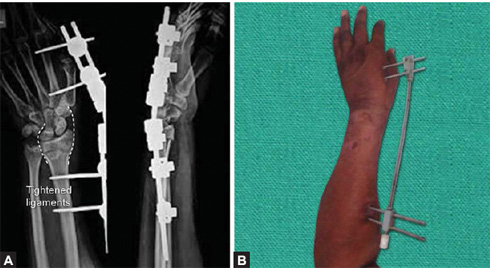

Figs. 1.45A and B: (A) X-ray of wrist joint AP and lateral views showing fixation of distal radius fracture by external fixator (tightened ligaments are shown by broken white lines). (B) clinical picture of distractor used for distal end radius fracture.